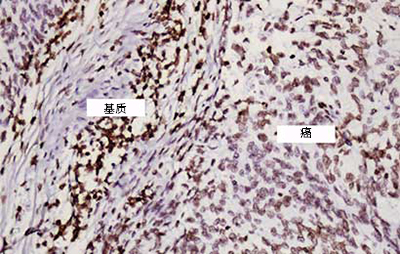

宫颈鳞状细胞癌–强HPV表达